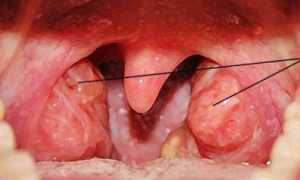

Эта болезнь характеризуется воспалительным процессом, поражающим слизистую оболочку носа. Происходит ухудшение тонуса капилляров, их стенки расширяются и тем самым вызывают стойкий отек слизистой.

Для вазомоторного ринита характерна следующая клиническая картина:

заложенность, затрудненное дыхание, что может иметь перемежающийся характер;

- чихание;

- водянистые выделения;

- зуд в носу;

- увеличение раковин носа;

- общая слабость.

На фоне постоянно заложенного носа могут появляться головные боли.